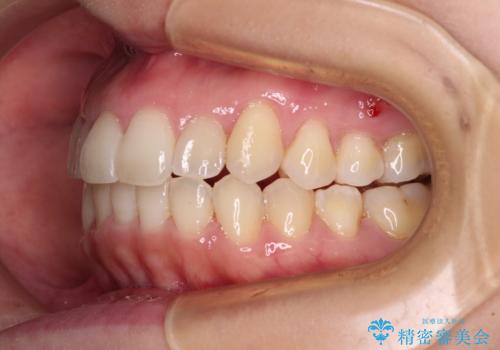

- 八重歯と前歯のデコボコを気にして来院された患者様です。

八重歯の他に、上顎歯列を狭窄しているという問題点がありました。

また、八重歯により上顎奥歯が前方に位置しており、咬み合わせの改善も必要な状況でした。